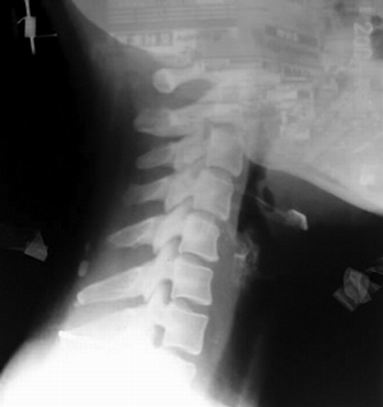

从侧面看,颈椎的部分向前弯曲,呈反括号状,如果颈椎的弧度消失或呈正括号状,就是颈椎反弓。人的脊柱由30多节椎骨组成,从正面看,脊柱是一条笔直的粗线,如果脊柱向左向右弯曲,不是一条直线,就是脊柱侧弯。(王真)